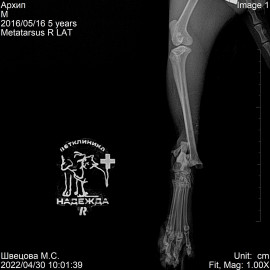

Наш пациент, кот, по кличке Архип.

Обратились к нам после автотравмы с жалобами на отсутствие опороспособности на правую заднюю лапу.

Было проведено рентгенологическое исследование.

Поставлен диагноз: перелом правой голени, вывих правого голеностопного сустава. Была проведена операция: остеосинтез правой голени, остеосинтез правого голеностопного сустава.

Снимок 3-4 после операции.